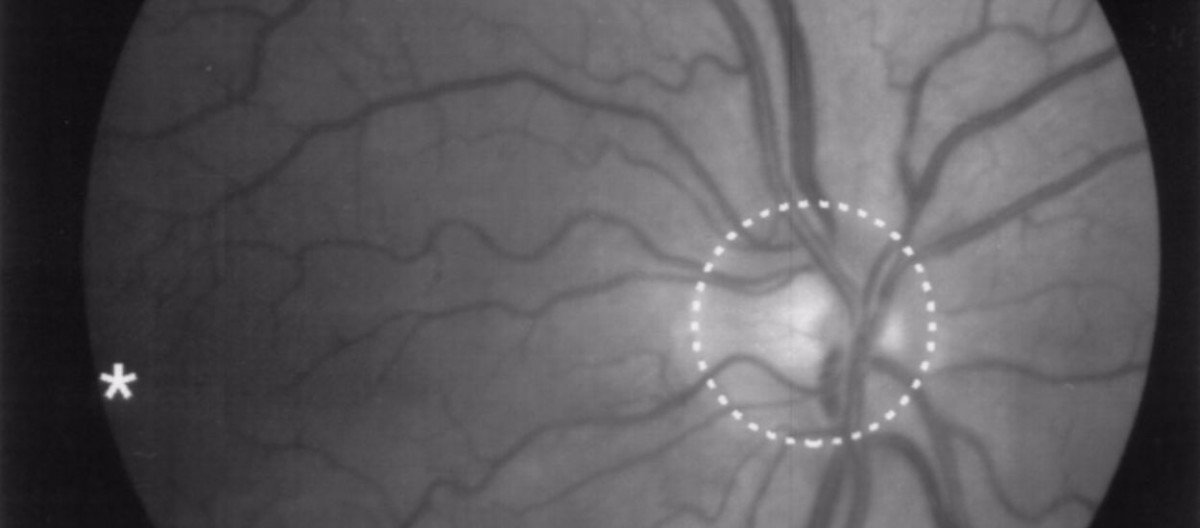

Bu tedavinin yaşlılığa bağlı makula(sarı nokta) dejenerasyonu* ile ileri derece retina hasarının tedavisinde iyi sonuçlar vereceği tahmin ediliyor.

Makula(sarı nokta)* : Retina tabakasının ortasında ve keskin görmeden sorumlu çok küçük bir alanıdır.

Makula dejenerasyonu, sarı noktanın hasar görmesi veya ilerleyen yaşa bağlı olarak fonksiyon kaybıdır. Yüksek tansiyon, sigara ve genetik nedenler, makula dejenerasyonuna sebep olan diğer önemli risk faktörleridir.